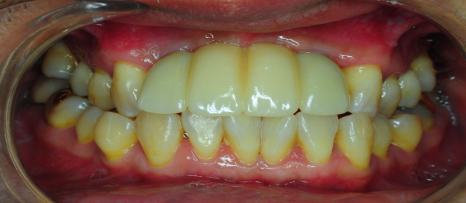

[스마일디 임플란트 사례 중 일부]

치료기간: 24.11.03일-24.12.03(약 1개월)

진행한 치료: 발치 후 임플란트

*치료 전후 사진은 환자의 동의하에 게재하였으며, 동일한 환경과 조건에서 촬영된 전후 사진입니다.